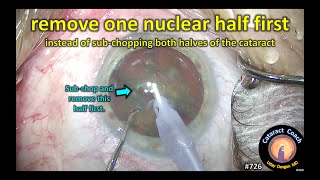

Small pupil cataract surgery management by Dr Bengebara Omar (Stretching + phaco, sped up *3) remove one nuclear half first in cataract surgery

remove one nuclear half first in cataract surgery What Does a Cataract Look Like Inside Your Eye? (Visual Representation)

Small pupil cataract surgery management by Dr Bengebara Omar (Stretching + phaco, sped up *3) remove one nuclear half first in cataract surgery

remove one nuclear half first in cataract surgery What Does a Cataract Look Like Inside Your Eye? (Visual Representation)